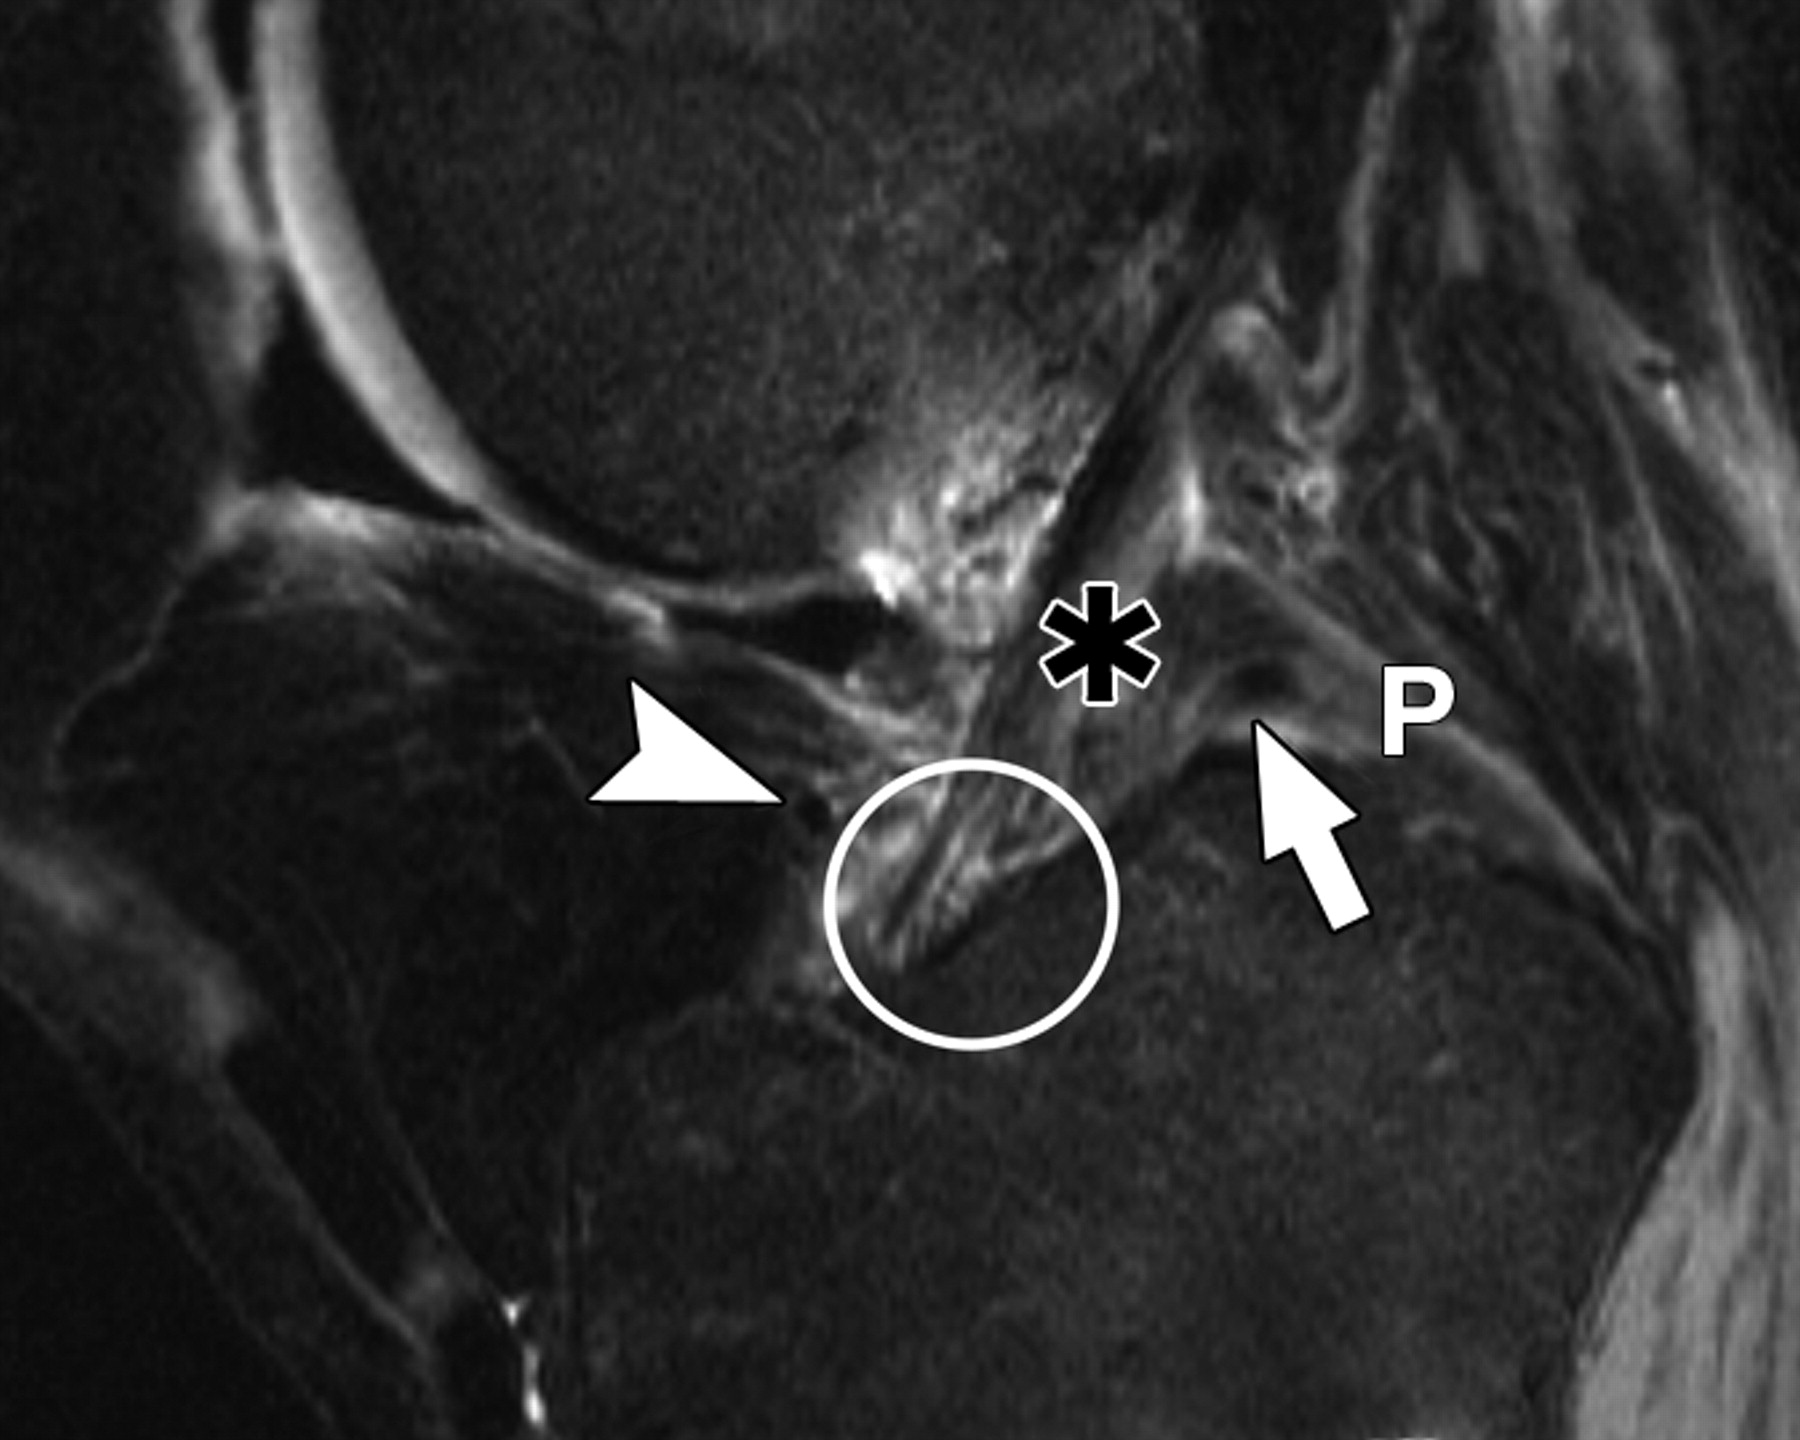

图5E-59岁男性,中等加权、脂肪饱和、快速自旋回波(TR/TE,3,700/29)3-T MR图像显示半月板后根和交叉韧带的解剖关系。

通过前交叉韧带(星号)的MRI图像显示外侧半月板后根的附着点(箭头)相对于内侧半月板的附着点稍靠前。圆圈表示前交叉韧带和外侧半月板前根的共同附着点。箭头表示膝前韧带。P =后交叉韧带。